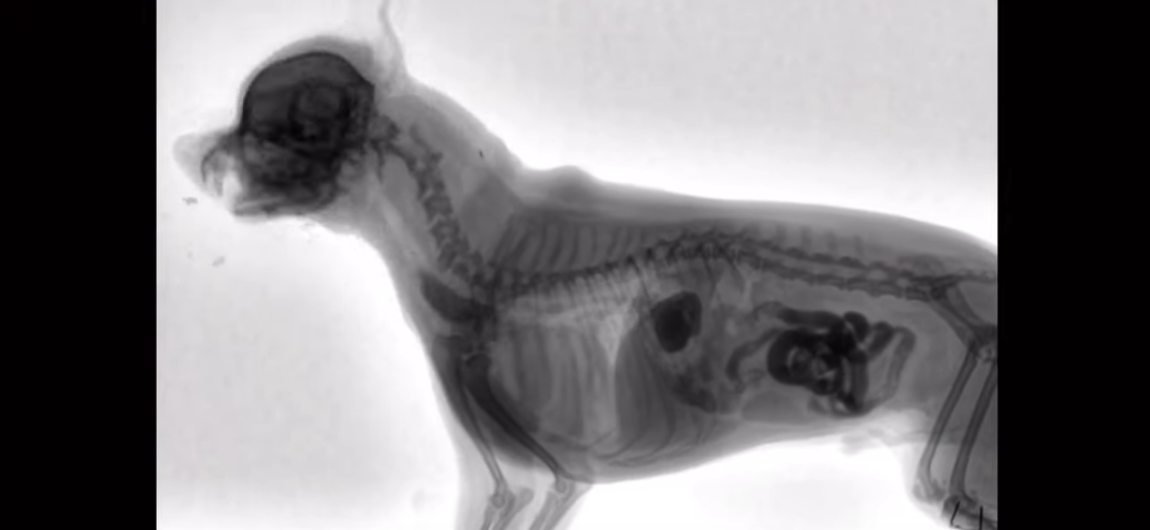

Que voit-on au rayons X quand un chien mange ?

Dans cette vidéo il est possible de voir ce qui se passe lorsque votre chien avale de la nourriture et de suivre le parcours de cette nourriture dans le système digestif du chien.

La technique utilisée ici est la fluoroscopie, un produit est ingéré par le chien ou injecté au besoin permet de générer un contraste permettant aux vétérinaires d’observer les différents organes aux rayons X.